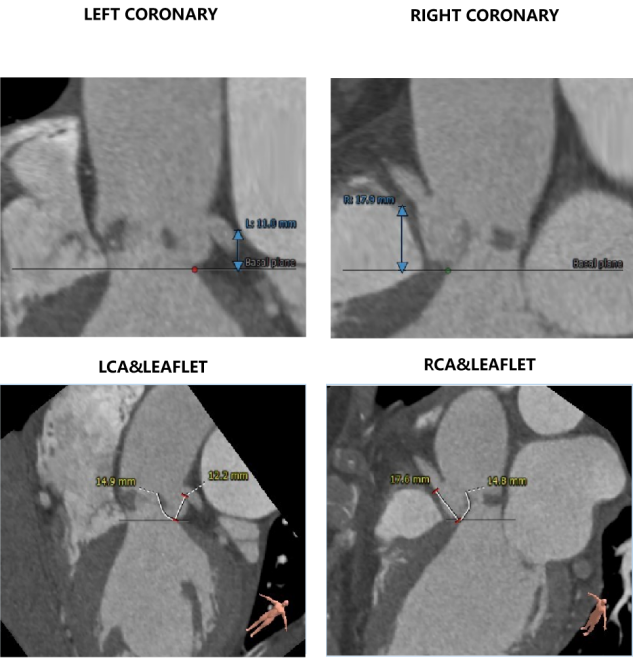

CT数据显示该患者为三叶三窦式主动脉瓣。

左冠开口高度11.0mm,右冠开口高度17.9mm,左冠高度较低,根据瓦氏窦内径和瓣叶长度综合判断,左冠存在一定堵塞风险;左室腔增大,心室壁未见明显增厚。